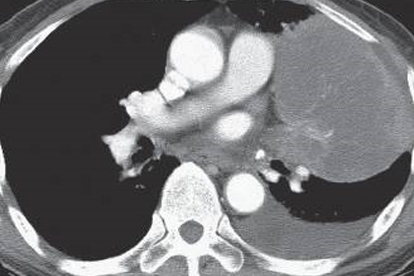

肺炎的診斷需要結合臨床癥狀、影像學檢查和實驗室檢查綜合判斷。單純發(fā)現肺部有炎癥表現不能直接診斷為肺炎。醫(yī)生會根據患者的病史、癥狀表現、胸部X光或CT檢查結果、血液檢查等做出準確診斷。對于非感染性肺部炎癥,治療重點在于消除病因和控制炎癥反應。